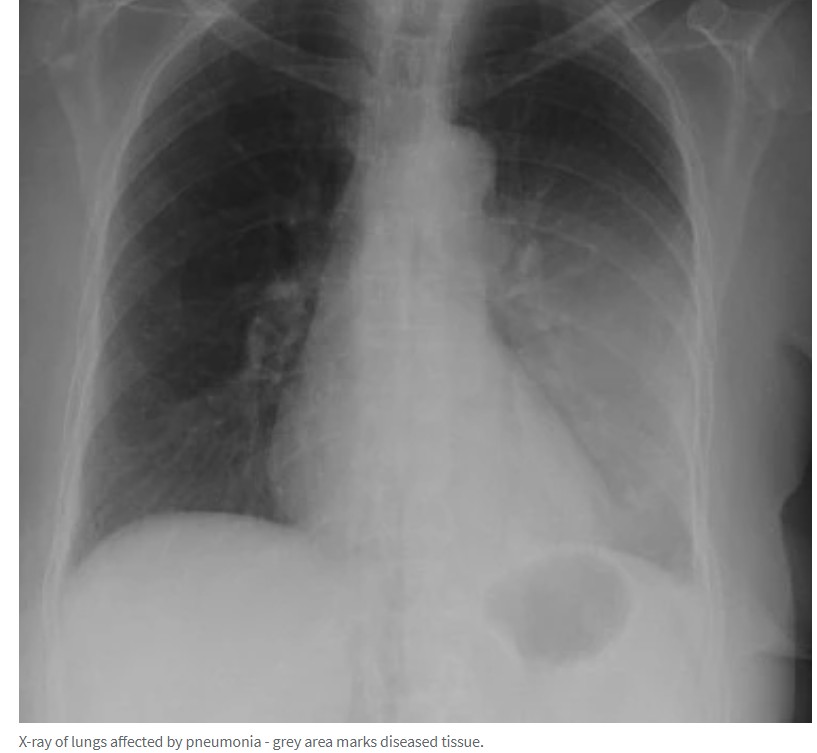

昆州抗生素短缺,肺炎病例激增,近两万名儿童感染!

据悉,由于抗生素短缺,昆州近两万名儿童患上了发病率急剧上升的肺炎。 卫生专家透露,用于治疗这种严重疾病的抗生素出现了长达三个月的短缺。 &quot;之所以称之为行走性肺炎,是因为这种疾病通常不会导 ...